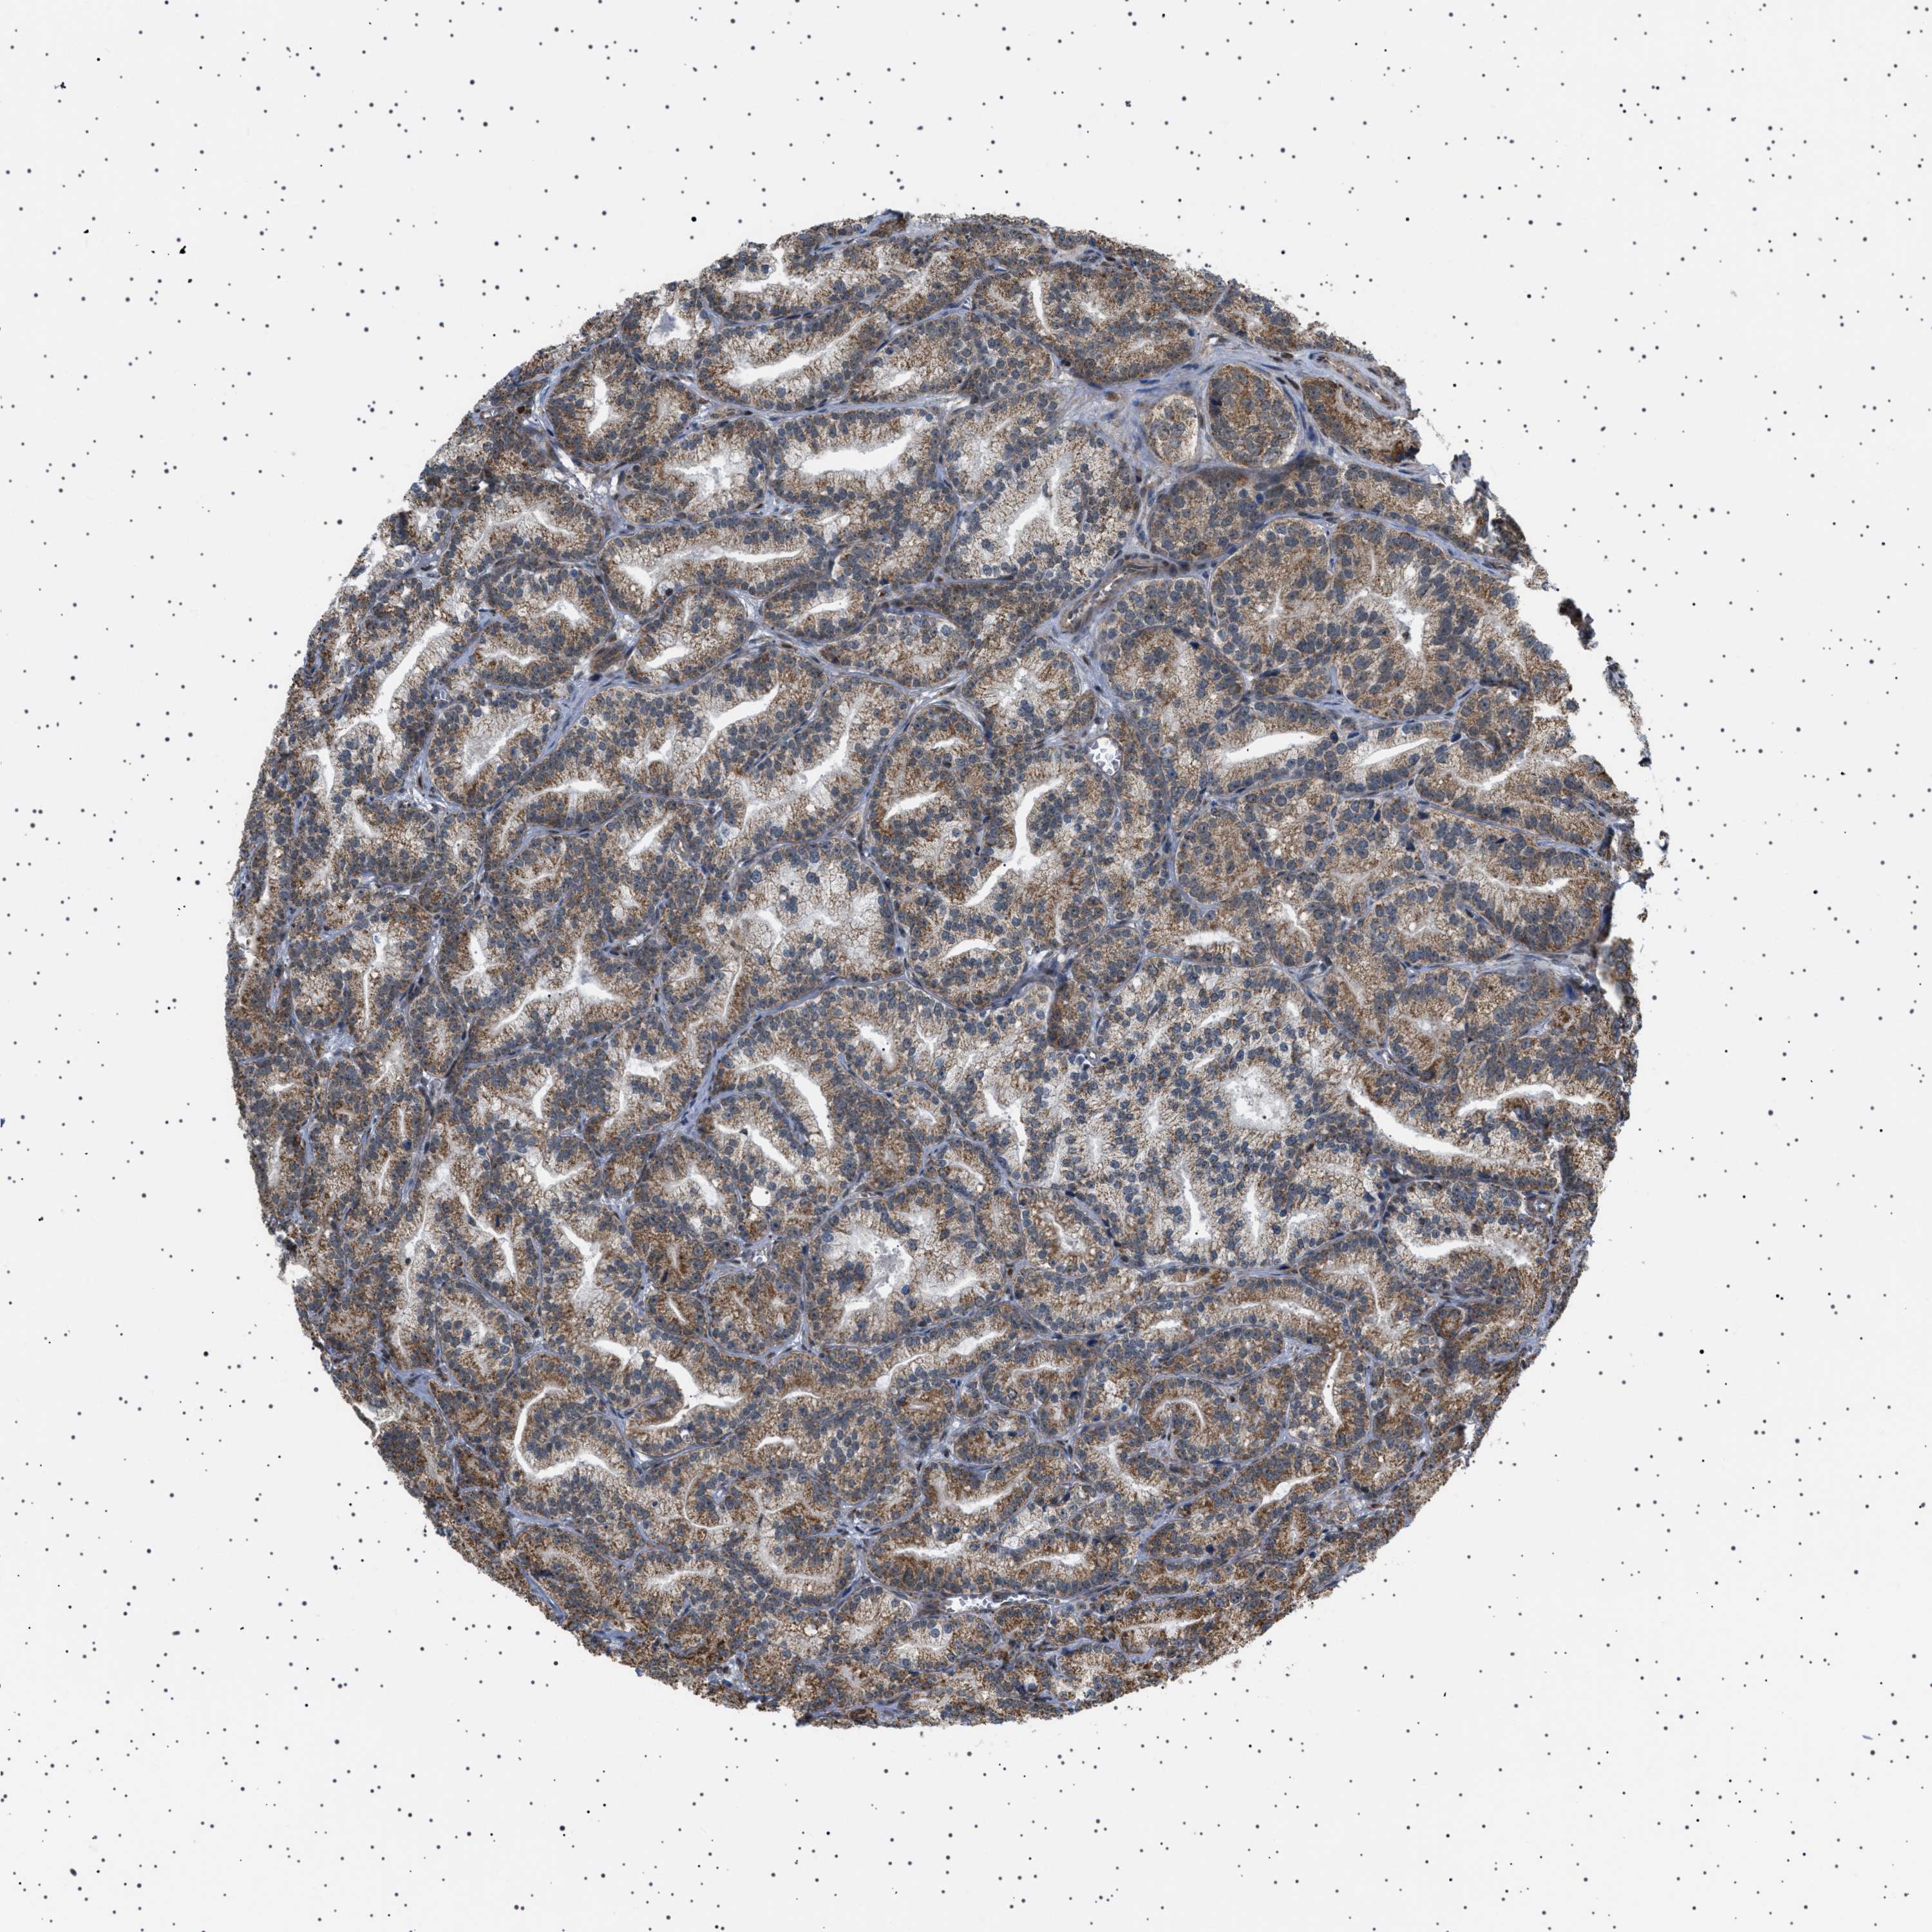

PROSTATE CANCER - Protein expressioni

A mouse-over function shows sample information and annotation data. Click on an image to view it in a full screen mode. Samples can be filtered based on level of antibody staining by selecting one or several of the following categories: high, medium, low and not detected. The assay and annotation is described here.

Note that samples used for immunohistochemistry by the Human Protein Atlas do not correspond to samples in the TCGA dataset.

Antibody stainingi

Antibody staining in the annotated cell types in the current human tissue is reported as not detected, low, medium, or high, based on conventional immunohistochemistry profiling in selected tissues. This score is based on the combination of the staining intensity and fraction of stained cells.

Each image is clickable and will lead to virtual microscopy that enables deeper exploration of all samples and also displays staining intensity scores, fraction scores and subcellular localization as well as patient and tissue information for each sample.

Antibody HPA017214

Staining

High

Medium

Low

Not detected

Intensity

Strong

Moderate

Weak

Negative

Quantity

>75%

75%-25%

<25%

None

Location

Nuclear

Cytoplasmic/membranous

Cytoplasmic/membranous,nuclear

Adenocarcinoma, High grade

Adenocarcinoma, Low grade